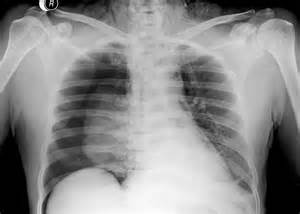

Rentgen – ilkin müayinədir, pnevmotoraksı və bəzən də plevrada mayeni dəqiqləşdirən müayinədir.

Plevrada mayeni rentgen göstərə bilər. Qabırğa-diafraqma cibinin düzləşməsi, plevrada homogen kölgəlik, Damuaze xətti mayenin rentgenoloji əlamətləridir. Qabırğa-diafraqma xəttinin düzləşməsi plevrada ən azı 250 ml mayenin olduğunu göstərir. Lakin, mayeni görmək üçün ən həssas müayinə USM-dir.